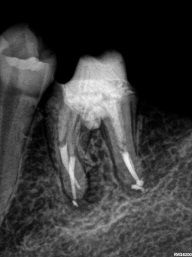

Perfurações dentarias são complicações no tratamento de canal que na maioria dos casos resulta em um prognóstico desfavorável, pois permite a entrada de microrganismos nos tecidos que envolvem o dente. Em alguns casos, devido ao seu difícil diagnóstico, acesso limitado, tempo decorrido ou tamanho da perfuração resultará em um desafio para o profissional conseguir um selamento adequado da área, sendo muito importante o conhecimento sobre o material que será empregado.